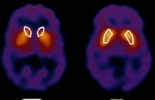

تظهر الأبحاث العلمية يوماً بعد يوم الاختلاف بين الرجل والمرأة في كل شيء تقريباً، وفي هذه المقالة حقائق جديدة توصل إليها العلماء تأتي لتشهد على صدق هذا القرآن..........